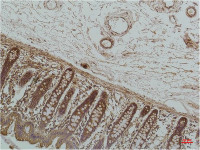

SGCE antibody [N1C1] detects SGCE protein at cytosol on mouse heart by immunohistochemical analysis.

Sample: Paraffin-embedded mouse heart.

SGCE antibody [N1C1] (GTX116453) dilution: 1:500.

Antigen Retrieval: Trilogy™ (EDTA based, pH 8.0) buffer, 15min